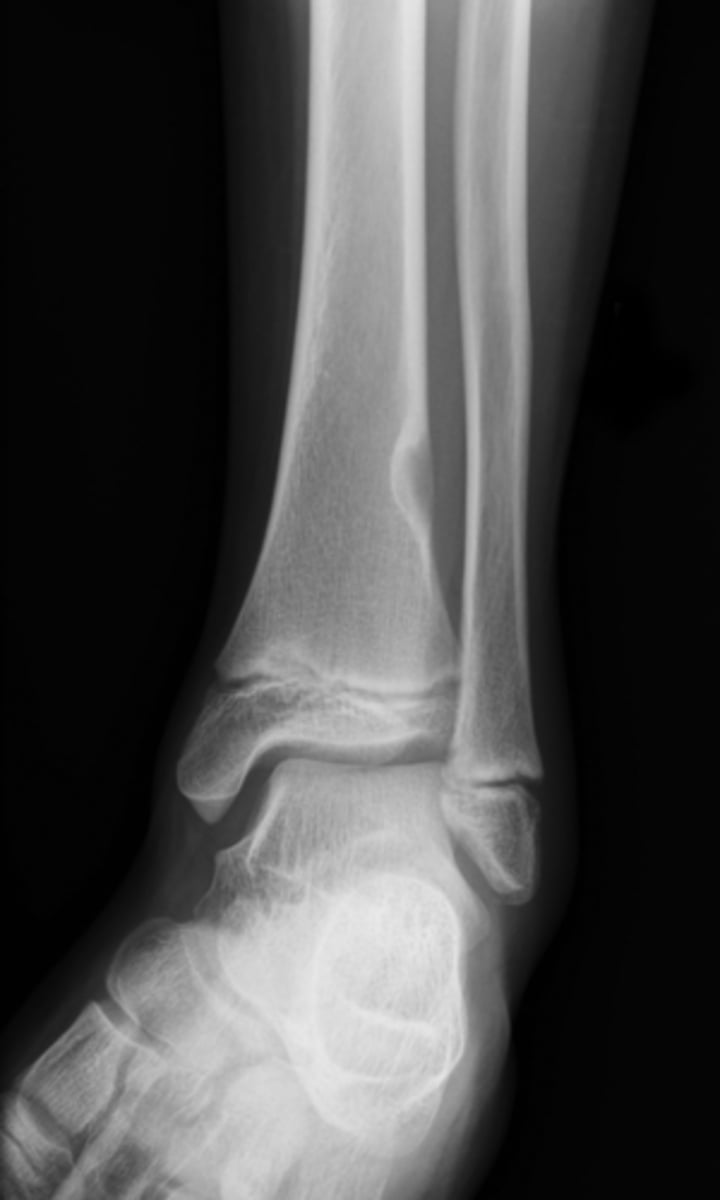

Pathologic fracture

Non-ossifying fibroma with _____

<p>Non-ossifying fibroma with _____</p>

Non-ossifying fibroma

- Kids (<20 y.o.)

• Fibrous cortical defect (older term)

• Younger patient and smaller <2-3 cm

- M:F, 2:1

- Lower extremities

- Present in 30-40% of normal children

- Most asymptomatic (unless pathologic fracture)

<p>- Kids (&lt;20 y.o.)</p><p>• Fibrous cortical defect (older term)</p><p>• Younger patient and smaller &lt;2-3 cm</p><p>- M:F, 2:1</p><p>- Lower extremities</p><p>- Present in 30-40% of normal children</p><p>- Most asymptomatic (unless pathologic fracture)</p>

- Solitary

- Eccentric

- Geographic

- Multiloculated

- No malignant transformation

State the radiographic features of non-ossifying fibroma

<p>State the radiographic features of non-ossifying fibroma</p>